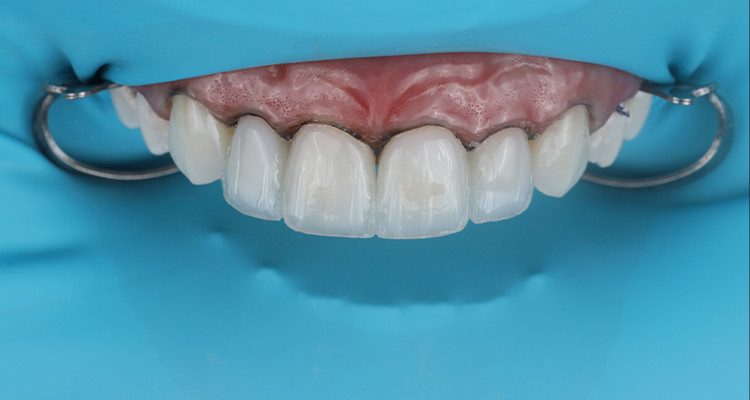

3 | Condicionamento ácido total de superfície com Condac 37, com isolamento absoluto modificado e fios retratores posicionados.

11 | Aspecto final das restaurações após acabamento e polimento.